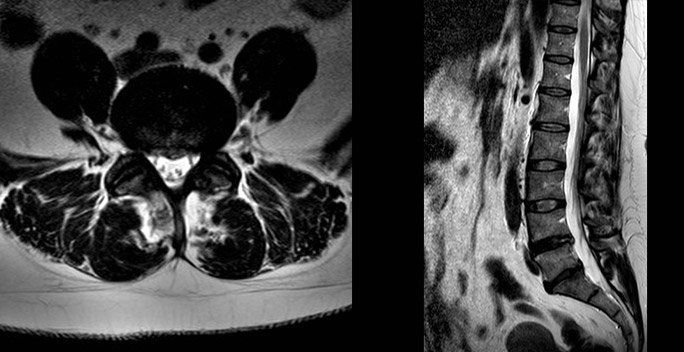

In the back, disc prolapses are one of the most common findings. On MRI scan a prolapsed disc looks like a dark oval structure bulging into the spinal canal on the cross- section view. When it touches a nerve you will feel pain radiating from your back down the leg and this is known as sciatica.

What does a disc prolapse look like?

The pictures above are of an MRI scan showing a prolapsed disc. The dark oval structure in the centre is a disc and the bulge coming off the base is the “prolapsed disc” protruding into the spinal canal on the cross- section view. In the image on the right the disc prolapse can be seen as a circle behind the spinal bones. When it touches a nerve you will feel pain radiating from your back down the leg and this is known as sciatica.

When do I need a re-scan?

The images below show a resolved disc prolapse. There is no longer black material in the spinal canal. Whether you need a new scan will depend on how you respond to treatment, clinical assessment and if it is felt you may benefit from an operation.

Can my disc prolapse heal itself?

Yes. The body has a remarkable capacity for repair. This prolapse resolved within 3 months. The body shrinks the disc by absorbing water, when this process is complete your pain will improve. The majority of discs will improve given long enough. My role is to guide you through the options, and step in if your life is on hold and waiting is unacceptable you may be a candidate for surgery on the lower back.